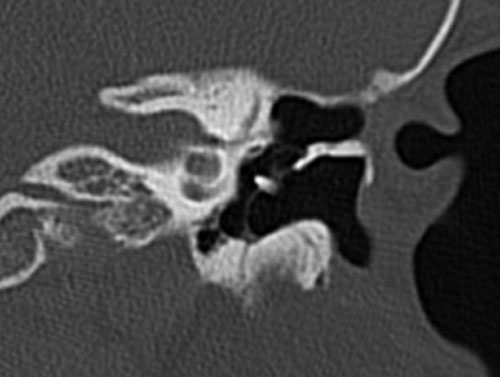

Bên trái là hình ảnh cholesteatoma lớn trong hòm nhĩ phải với phá hủy thành bên của hòm nhĩ.

Thân xương đe, nằm bên ngoài chỏm xương búa, cũng bị ăn mòn (mũi tên).